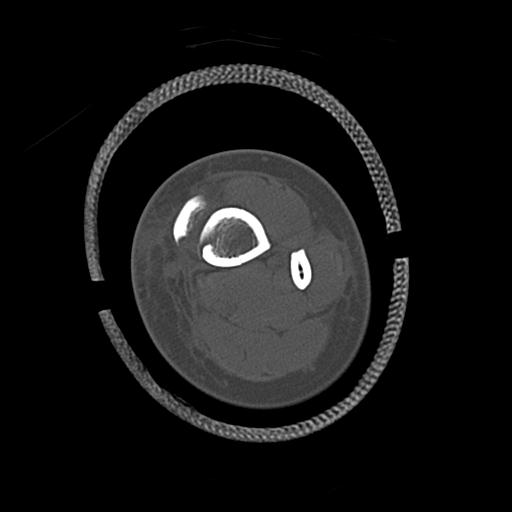

110211 1/6 1/8 左前腕 4R 15歳男性 橈骨骨幹部骨折